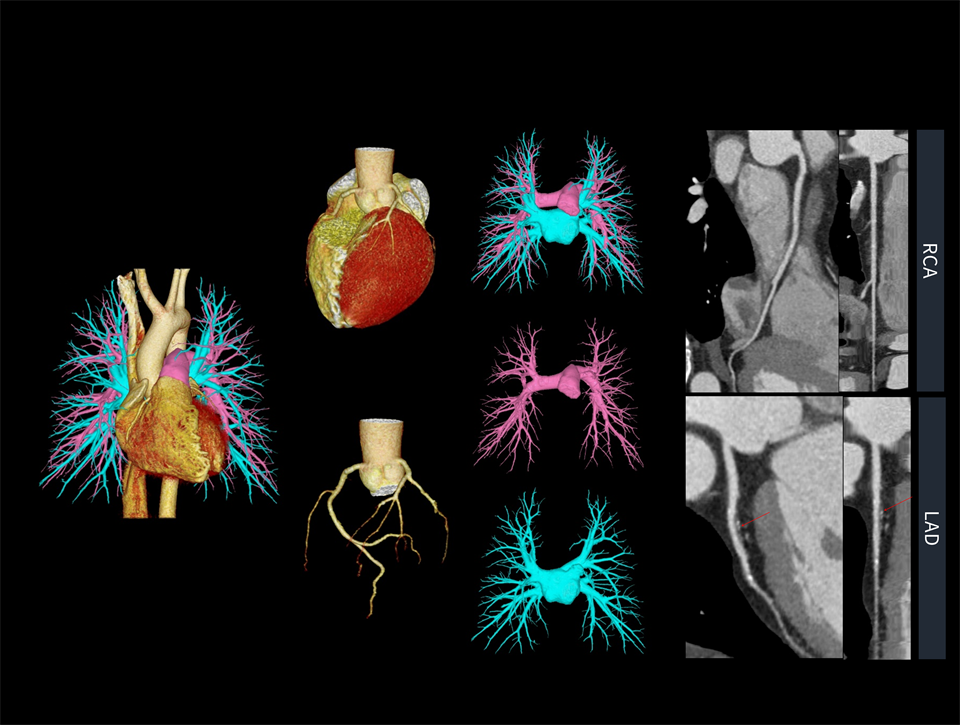

CardioBoost

Algoritm de reconstrucție bazat pe inteligență artificială, special conceput pentru imagistica cardiacă, care oferă o rezoluție spațială excepțională și capacitate avansată de suprimare a artefactelor.

CardioXphase

Selecție optimă de fază bazată pe inteligență artificială, care permite obținerea unor imagini coronariene CTA de înaltă calitate și reduce efortul tehnicienilor pentru procesarea și reconstrucția imaginilor.

CardioCapture

Prin utilizarea unei corecții inteligente a mișcării, cu ajutorul unui algoritm coronarian bazat pe inteligență artificială, rezoluția temporală pentru imagistica cardiacă a fost îmbunătățită până la 25 de milisecunde.

Reducerea zgomotului imaginii, oferind o vizualizare mai clară a arterelor coronare și îmbunătățirea contrastului în interiorul vaselor cu stent.

Îmbunătățirea delimitării contururilor plăcilor, cu o diferențiere mai clară între plăcile dure și cele moi.

Permite o extragere mai precisă a vaselor grefate și o vizualizare îmbunătățită a vaselor distale, sprijinind medicii în evaluarea mai corectă a prognosticului pacienților.

Selectarea automată a celei mai bune faze îmbunătățește calitatea imagisticii coronariene.

Îmbunătățirea afișării arterelor coronare și reducerea artefactelor de mișcare prin algoritmi AI.

O rezoluție temporală de 25 milisecunde crește considerabil calitatea imagisticii cardiace pentru pacienți cu ritm cardiac neregulat.